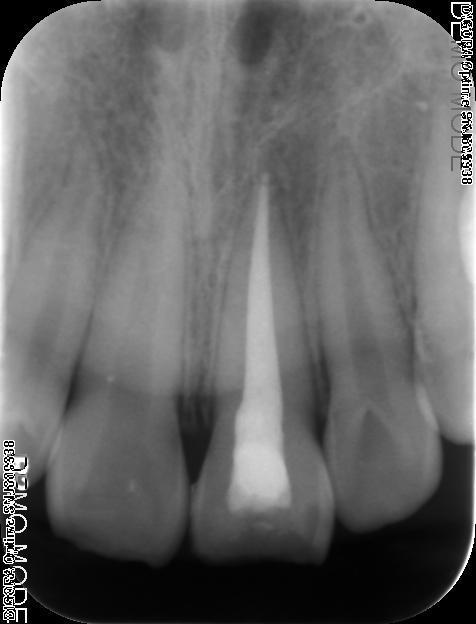

诊断:#21冠折 治疗:#27碧兰麻下开髓,清理髓腔及根管,双氧水和生理盐水交替冲洗,测WL,拍片试尖达工作长度,根管内导入糊剂,侧压充填中下段,热牙胶充填上段,X线示恰填,树脂充填修复。

外伤致穿髓可行一次性根备根充